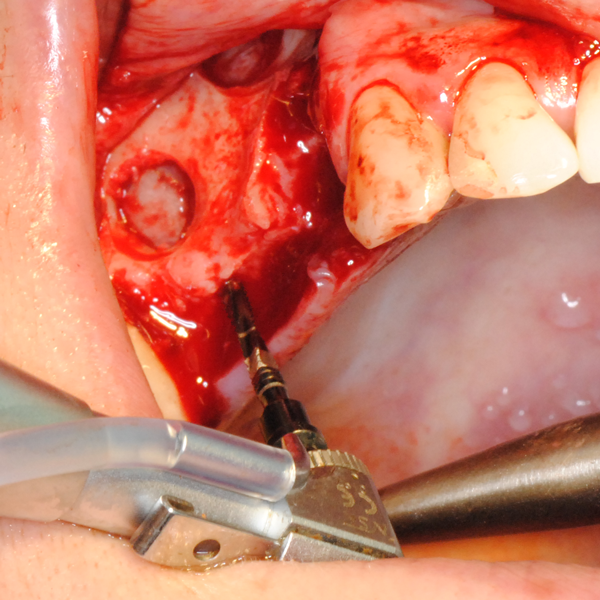

Отворен максиларен синус в началото на интервенцията. Случаят е интересен със следното - твърде атипична форма на трепанационния отвор. На какво се дължи на това - на лошо планиране на оперативния достъп или на нещо друго? Дължи се на факта, че отначало въпросната намеса беше планирана като балонен синуслифт; за съжаление обаче мембраната на синуса се разкъса и надуването на балона стана невъзможно.